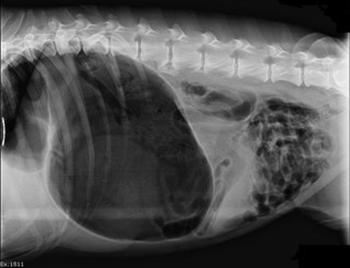

Рис. 3 - Крововиливи у черевну порожнину (свиня)

У собак превалюють зміни, характерні для геморагічного діатезу. Крововиливи мають вигляд великих розлитих гематом.

Обширні гематоми утворюються в м’яких тканинах навколо трахеї, в середостінні і в інших місцях. В порожнині перикарду, грудній, рідше - в черевній порожнинах виявляють 0,2 - 1,5л рідкої крові, інколи з рихлими згустками.